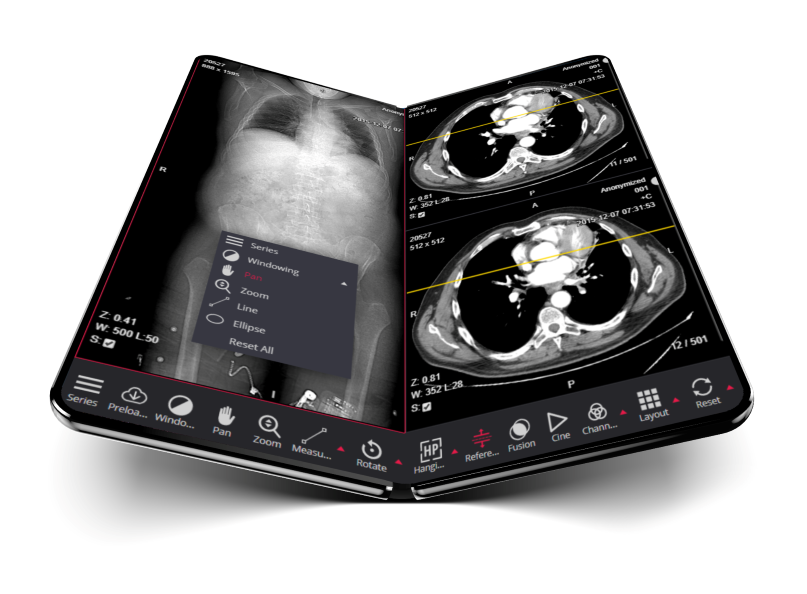

پرونـده الکترونیـک بیمـار

ثبت الکترونیکی سلامت (EHR) و یا مدارک الکترونیکی پزشکی (EMR)، به مجموعه نظام مندی از اطلاعات سلامت بیمار و جامعه الکترونیکی ذخیره شده در فرمت دیجیتال دارد. این سوابق را میتوان در سراسر مراکز بهداشتی درمانی مختلف به اشتراک گذاشت. سوابق از طریق، سیستمهای اطلاعات سازمانی وسیع متصل به شبکه یا دیگر شبکههای اطلاعات و مبادلهای به اشتراک گذاشته میشود. EHRها ممکن است شامل طیف وسیعی از اطلاعات، از جمله جمعیت، سابقه پزشکی، دارو و آلرژی، وضعیت ایمنسازی، نتایج آزمایشها، تصاویر رادیولوژی، علائم حیاتی، آمار شخصی مانند سن و وزن، و اطلاعات صورت حساب باشد.